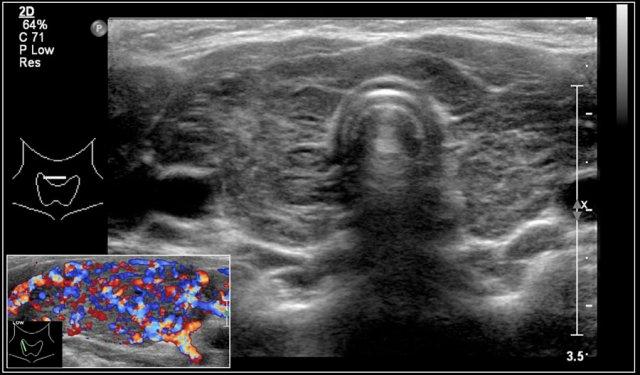

Đây là hình ảnh của một bé gái 16 tuổi mắc cường giáp.

Tuyến giáp to lan tỏa với tình trạng sung huyết.

Chẩn đoán cuối cùng là bệnh Graves.

Trong bệnh Graves, tuyến giáp cũng to ra và cho thấy sự tăng tưới máu.

Trên siêu âm Doppler màu, hình ảnh này được mô tả như một địa ngục lửa với màu đỏ và xanh.